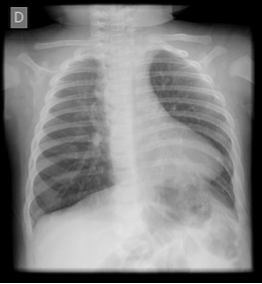

Após a suspeita clínica de Tetralogia de Fallot recomenda-se a realização de eletrocardiograma e radiografia torácica.

O Rx pode mostrar o aspecto de "coeur en sabot", uma expressão já classica que compara silhueta cardíaca à de uma botina ou um tamanco. O ventrículo direito hipertrofiado causa uma sombra apical arredondada com a ponta levantada para cima, de modo que ela está situada mais alta do que o normal acima do diafragma.